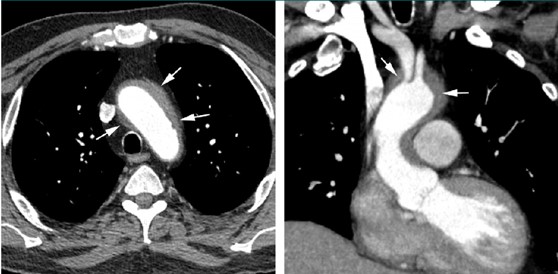

胸部造影CT

右房と心房中隔に限局した壁肥厚を認める。同部位には不均一な造影効果を認める。

右冠動脈の一部は肥厚した壁内を走行しているが、明らかな狭窄は指摘できない。

<心大血管病変>

• 右心房壁に濃染する腫瘤形成(33%)

• 大血管壁に沿った軟部影(coated aorta) (67%)